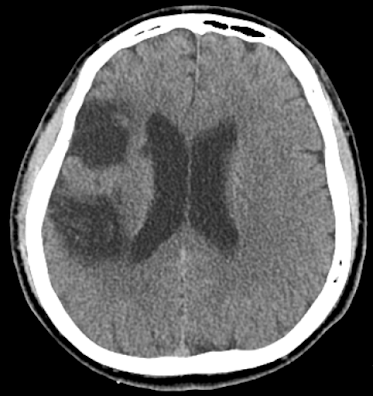

所幸病人恢復良好,至加護病房後左手左腳的力氣即有改善,核磁共振仍顯示右腦中等範圍的梗塞,但血管有通,病人的循環足夠其使用。之後轉病房,做了 14 天復健,再下轉到東區分院接續復健(PAC)。

圖四. 陳先生中風的區域為右側中大腦動脈供應區,但很巧的是,掌管左手左腳力氣的「運動皮質」(Primary motor cortex) 僅被傷到一點點,可以說閃過了這次的中風,我想是因為他個性善良,過去做了許多的善事